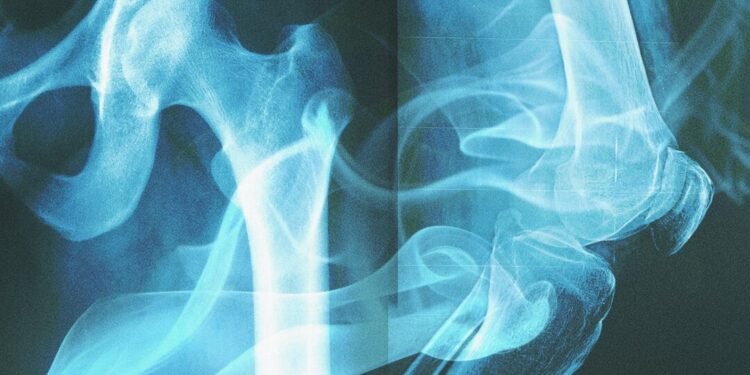

The scientific process involved sophisticated molecular analysis techniques that can detect microscopic changes in bone structure caused by smoking. These changes create distinct patterns that remain stable even after burial in various soil conditions for hundreds of years.

The concept of bones “remembering” cigarettes might sound mystical, but it’s rooted in solid biochemistry. When individuals smoke, the toxic compounds from cigarettes enter their bloodstream and eventually become incorporated into their bone matrix. This process creates permanent alterations in the bone’s molecular structure that serve as an unmistakable fingerprint of tobacco exposure.

These molecular signatures are so distinctive and durable that they survive the natural decomposition process, remaining detectable even in skeletal remains that have been buried for centuries. This discovery opens up entirely new avenues for both historical research and modern medical understanding.